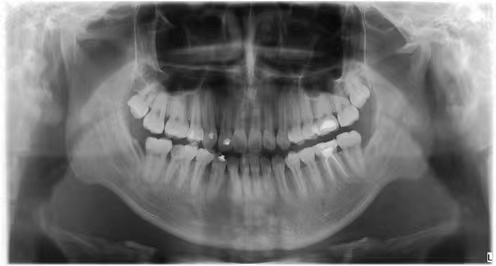

情况:不接受外科手术,在当地做了1年半的矫治,遇到困难无法进行。由外地正畸同行推荐来上海寻求非手术矫治的二手病例。武广增老师接收时的错合畸形情况,呈现严重的骨性反合偏合及侧方开合(图1-图10)。由于推荐其去口腔医院接受正颌外科手术遭到拒绝,武广增老师通过专业的检查、分析,制定一套详细的治疗计划,采用了磨牙推进器技术、武式辅弓技术等特色正畸手段获得明显效果(图2-1~图2-9)。治疗结束后也拍摄了相关照片(图3-1~图3-9)。

矫治前

图1